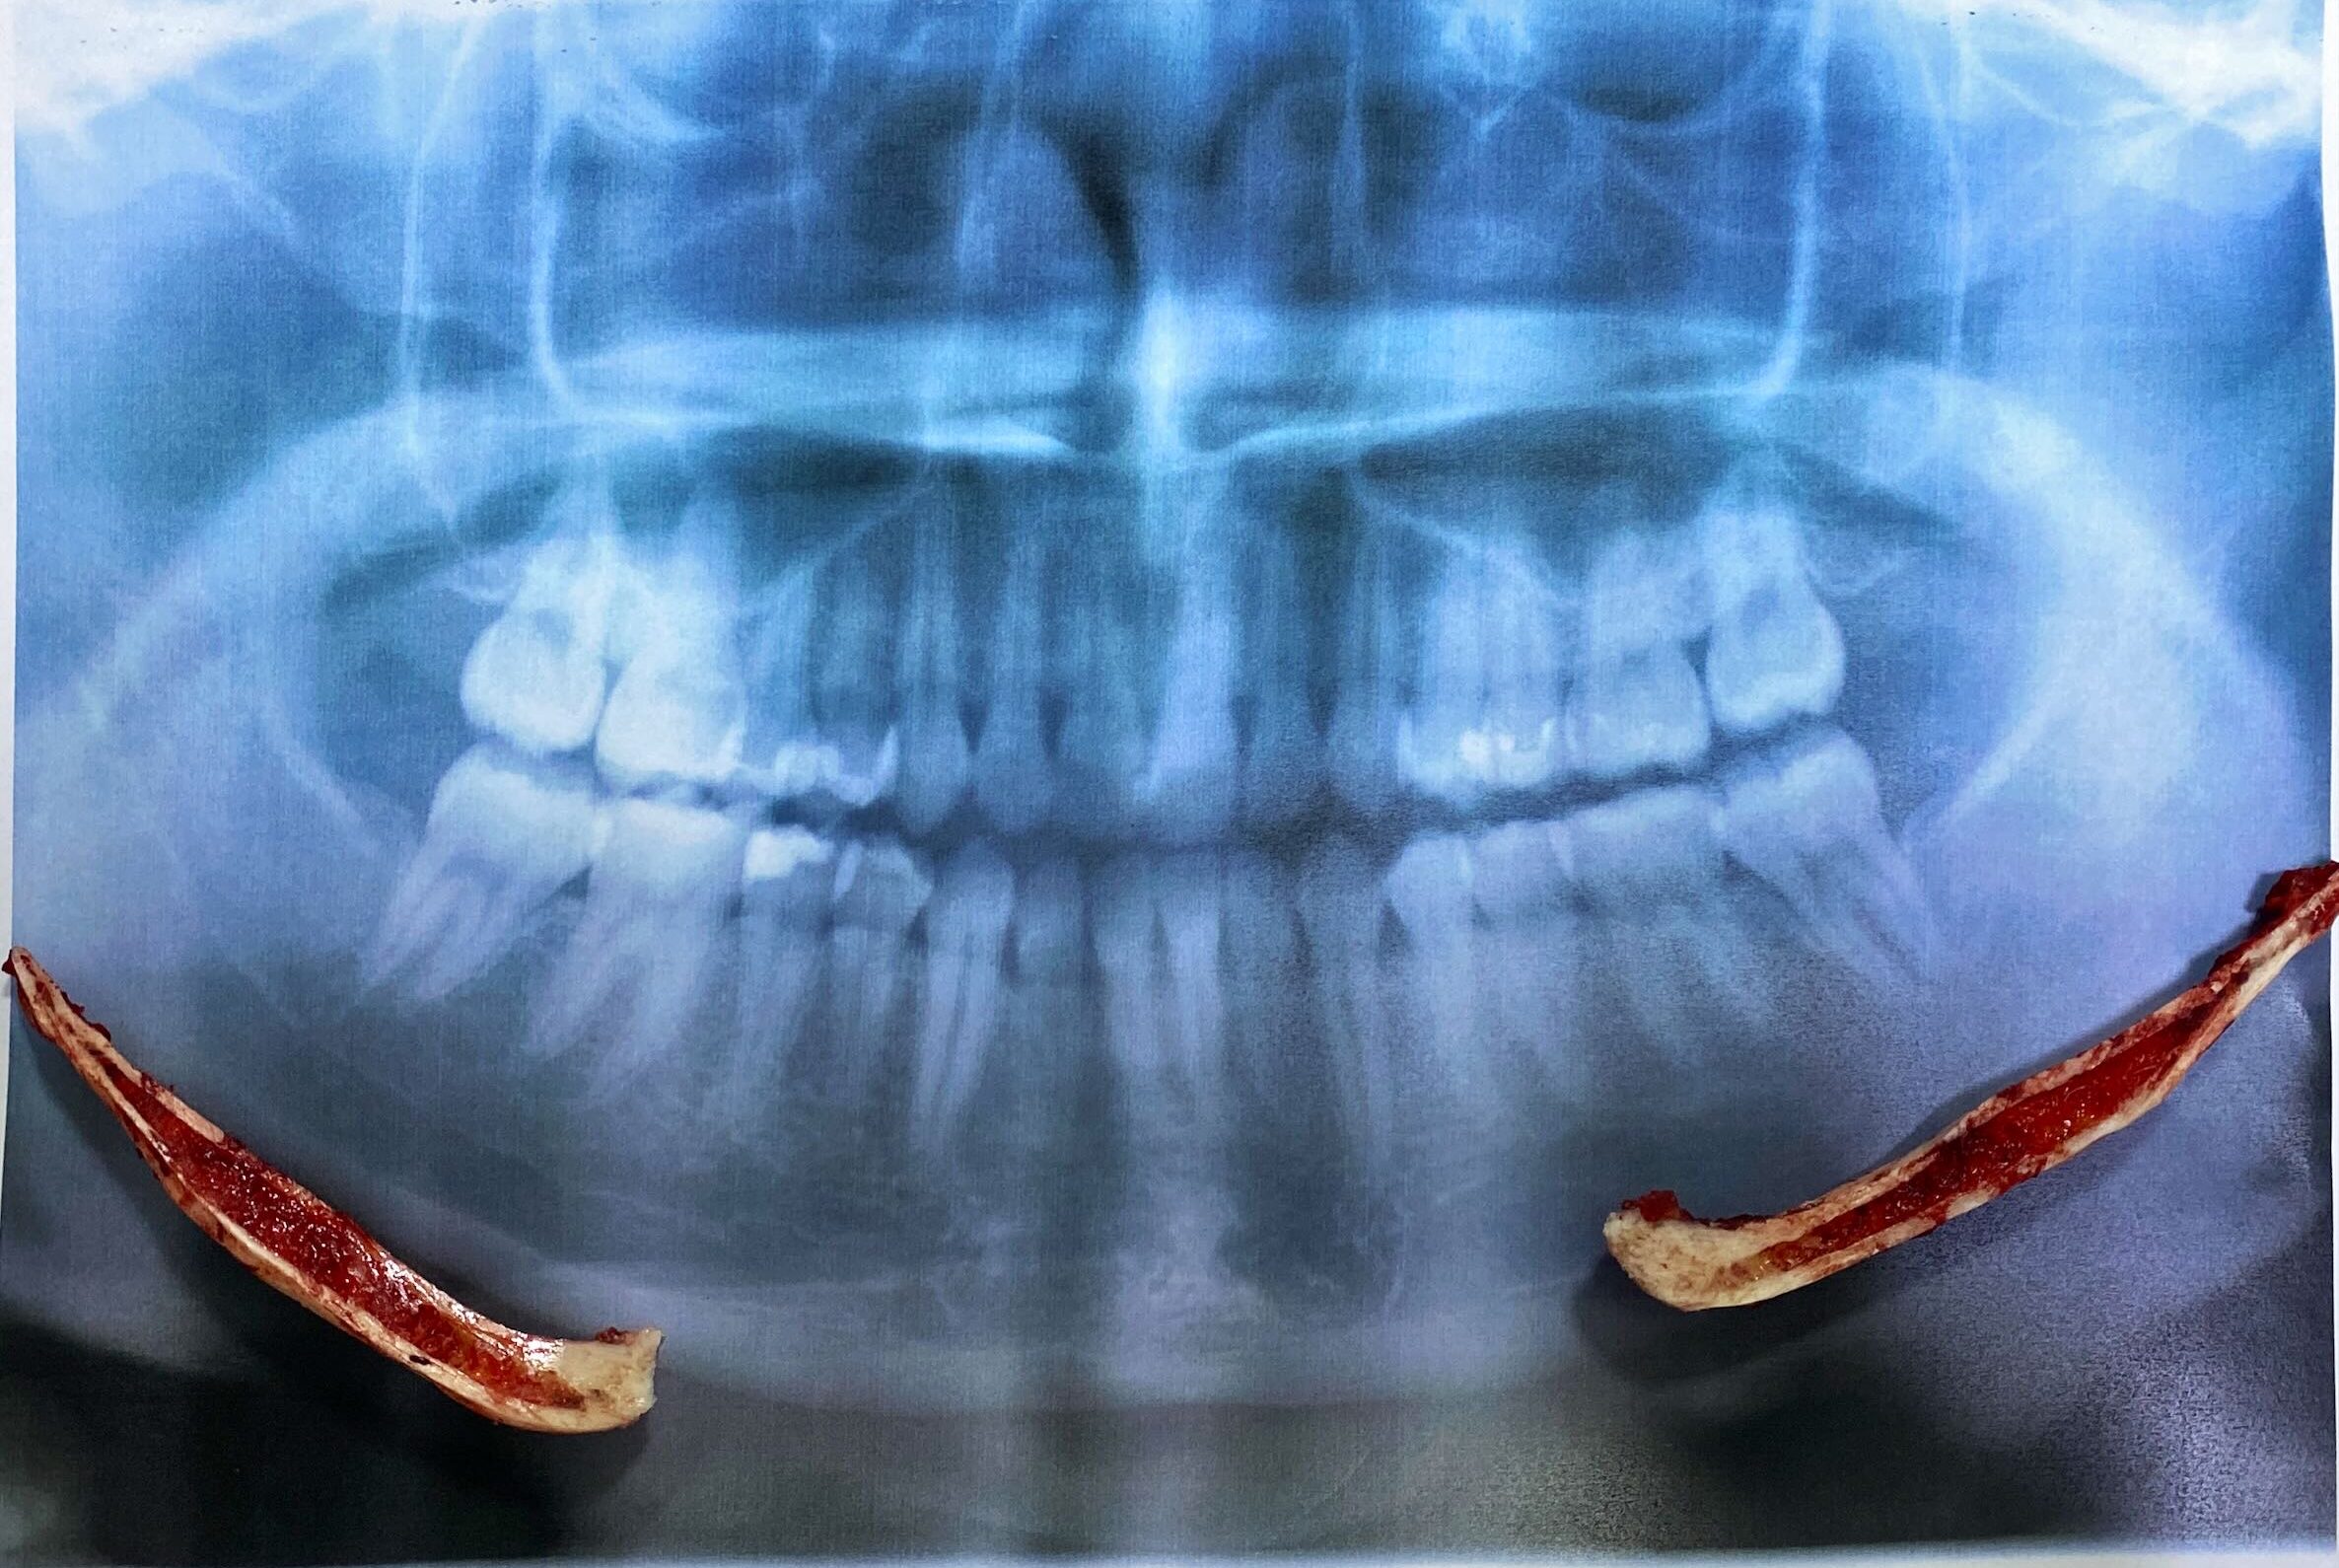

切除した骨をレントゲンに重ねてみました。

今回は患者様のご希望により、角を取ってフェイスラインまで綺麗なカーブを作りました。

角を取る手術の注意点は、顎の先端部分までスムースなカーブを描くラインを手術によって作ることです。

綺麗なカーブで骨をカットする必要があります。